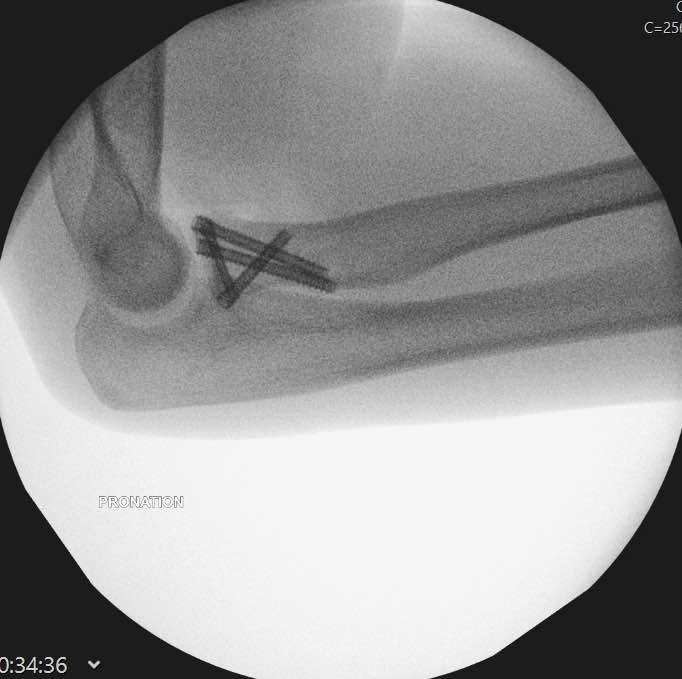

An elbow fracture-dislocation should get treatment as soon as possible. A dislocated elbow should be set back in place under sedation. This usually happens in the emergency department. A repeat x-ray will confirm that your elbow is in a congruent – acceptable position. After this happen, you will be typically referred to an orthopaedic surgeon for definitive treatment. Surgery usually involves the following:

- Fixation or arthroplasty of the radial head

- Fixation or suture fixation of the coronoid or anterior capsule

- Distal humerus fracture fixation, if present

- Repair of torn ligaments (LUCL +/- MCL) with suture anchors

- Olecranon fracture fixation, if present

Most terrible triad injuries require surgical management to restore the functionality of your elbow. Surgery involves addressing all the injury components in your elbow. These may include fixation or replacement of the radial head, fixation or suturing of the coronoid and repair of the avulsed ligaments of your elbow.